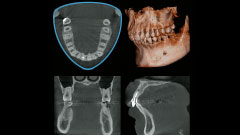

高精度な診断力で様々な歯科治療に貢献する

視野拡大による様々精密で質の高い治療

正確な

診断と治療

削除量を減らし

歯を保存する

不適合による

再治療を防ぐ